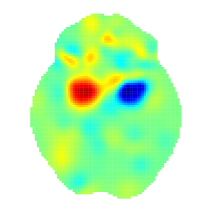

We use posterior intensities and to compare activation between the two types of studies in our sample, namely studies using verbal and studies non-verbal stimuli. We start with an ROI analysis. In particular, for each type and ROI we calculate the probability of at least one focus observed as explained above. These are shown in Table LABEL:tab:roi for a few ROIs, whereas a full brain analysis of the two types can be found in Appendix D. We see that even though the two types show similar patterns of activation, there several ROIs where the probabilities of at least one focus have credible intervals with little overlap. The main differences are found in the superior frontal gyrus, the middle frontal gyrus, the lateral occipital cortex, superior division and the inferior frontal gyrus, pars opercularis. A voxel-by-voxel comparison is also feasible. To answer this, we use the mean standardised posterior difference . This is shown in Figure 3. Large positive values indicate regions that are activated by verbal stimuli more than non-verbal stimuli. Such regions appear the occipital fusiform gyrus (, right). Based on the mean standardised posterior difference, regions mostly activated in studies using non-verbal are located in the middle frontal gyrus ().

Application of our model on a meta-analysis of working memory studies have given valuable insights regarding the data. While our maps for the overall pattern of WM activations (Fig. 2) and the differential effect of verbal vs. non-verbal WM tasks (Fig. 3) reflect previous findings found by Rottschy et al. (2012), our fully Bayesian approach allowed us to make direct inference on probability of any foci and expected number of foci. Our model found no regions with evidence of different rates of foci between verbal and non-verbal WM tasks (Appendix C, Table LABEL:tab:fullbrain2). Importantly, our model allows a meta-regression, and we examined the effect of age and found no strong effects but generally negative effects of age on the number of foci.